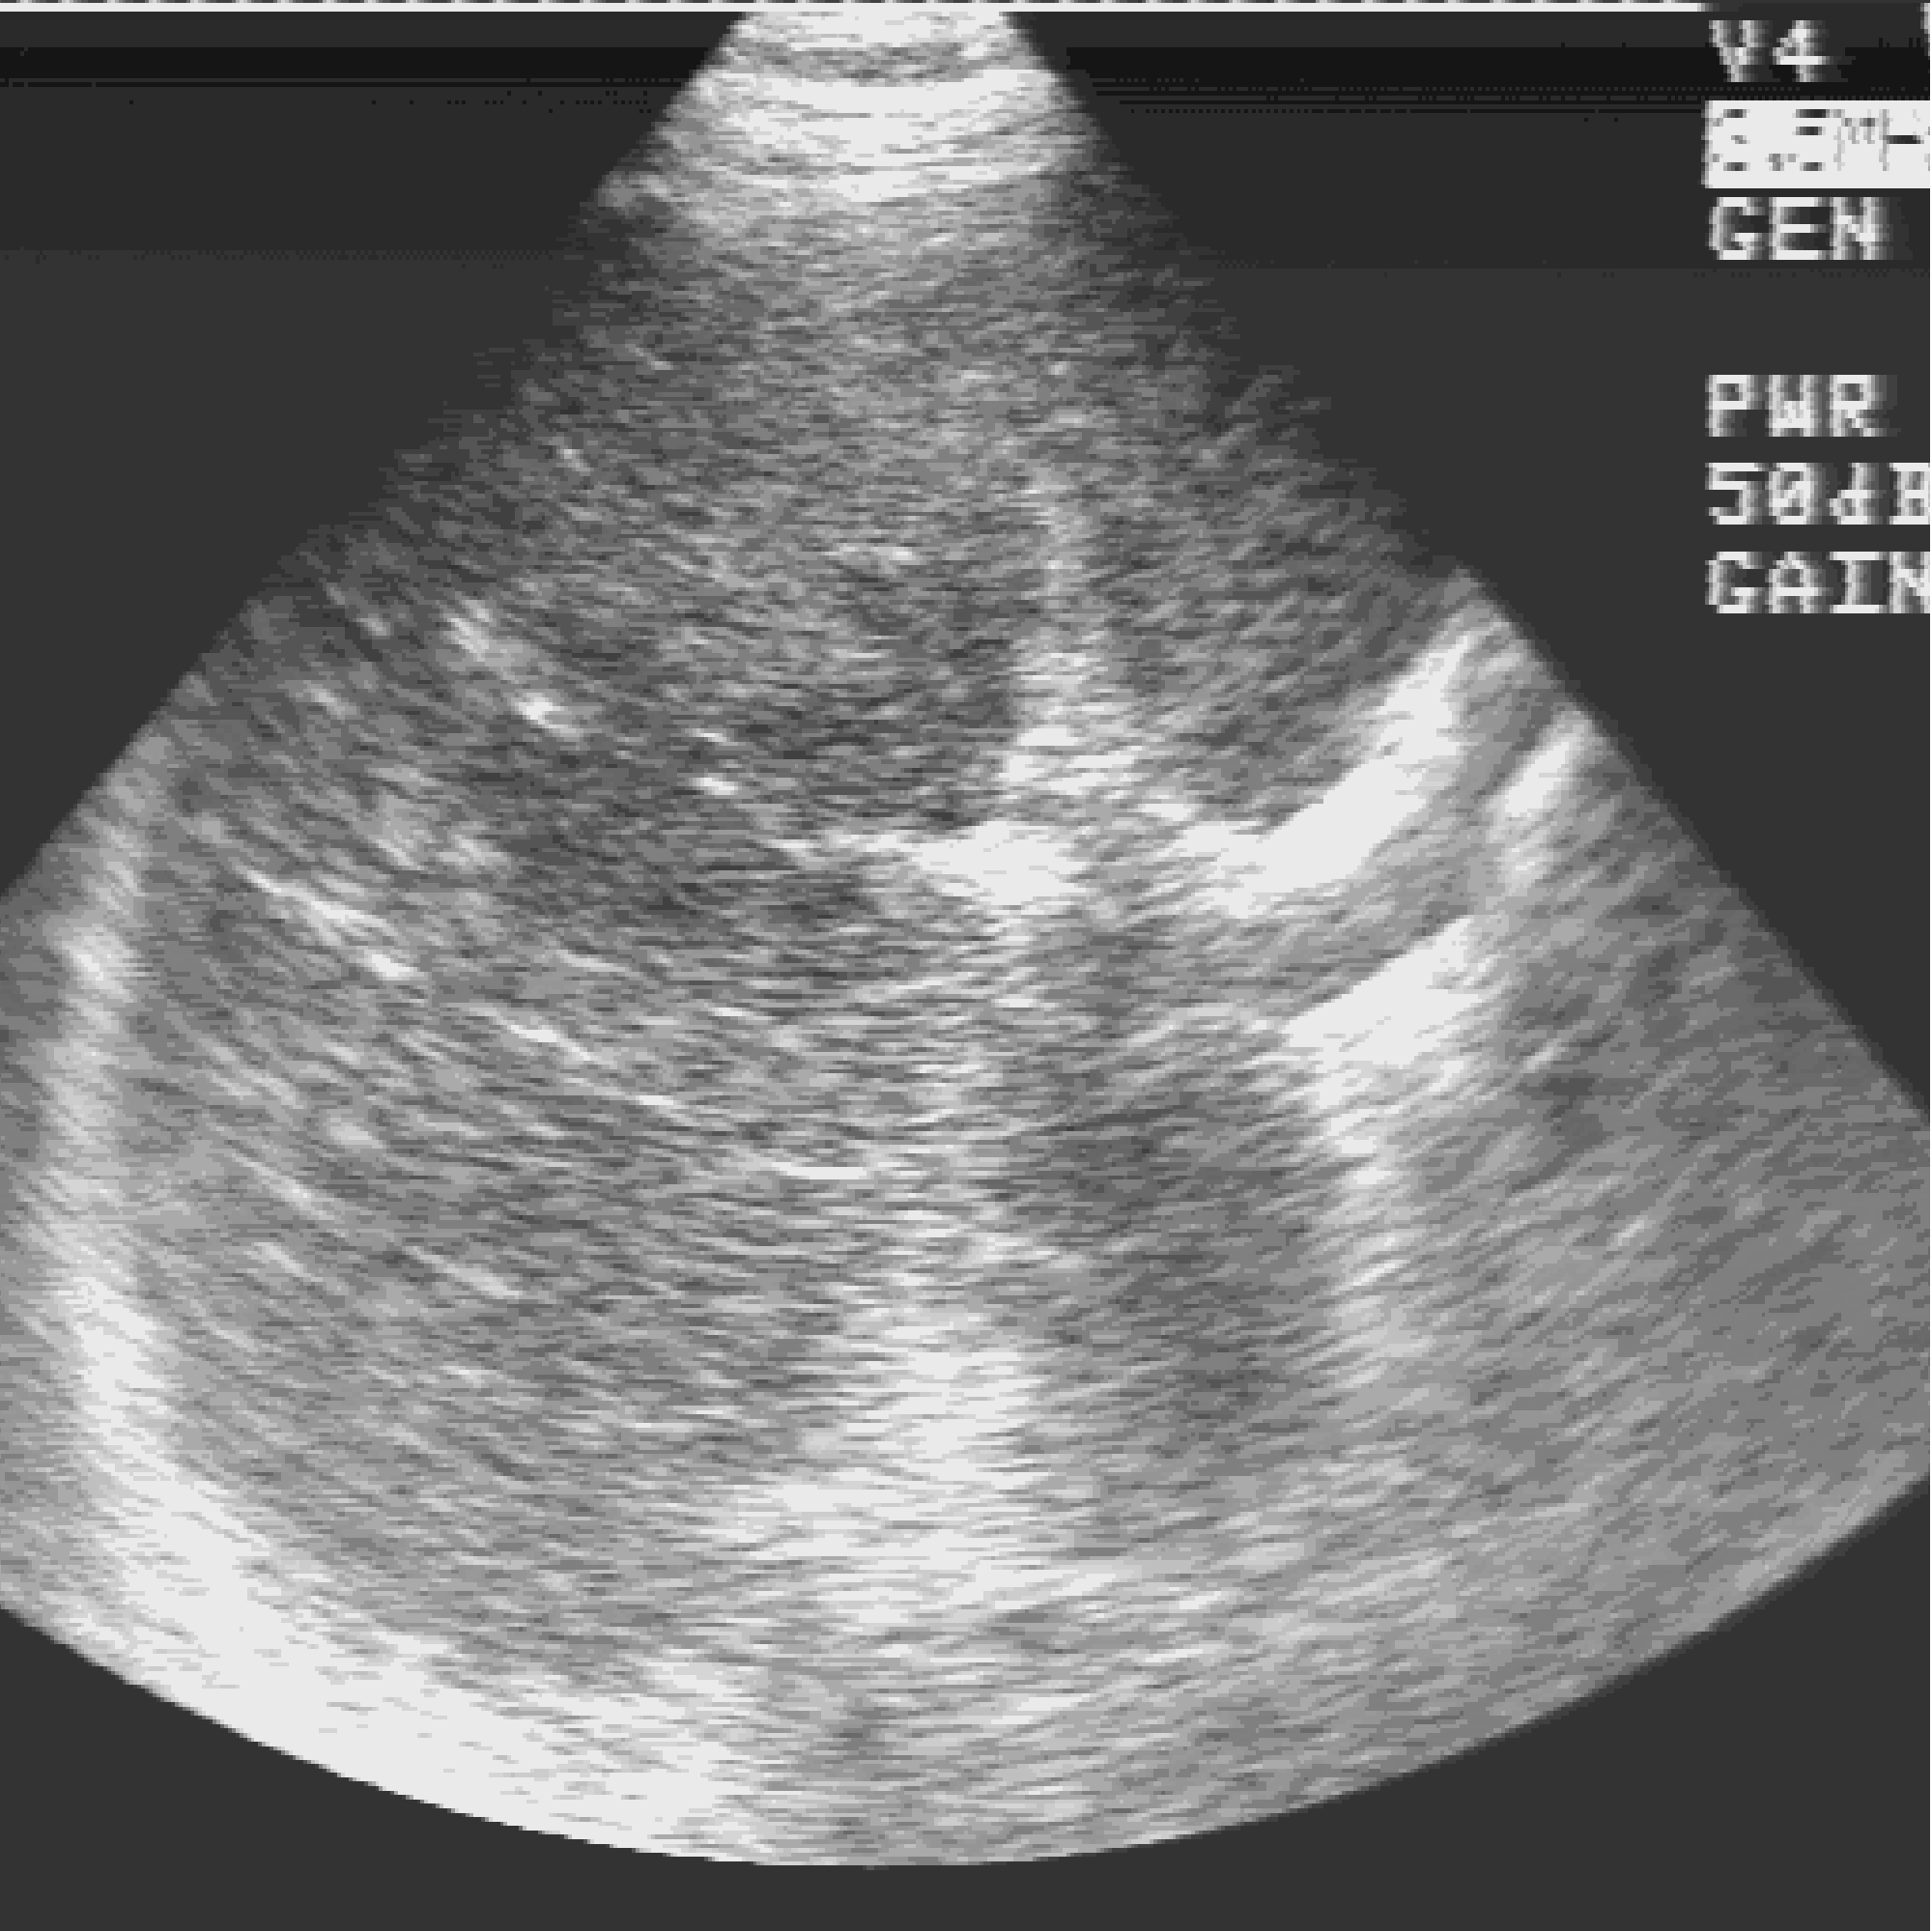

Это конфигурация для работы с изображениями. На рисунке видны два главных окна системы: окно Управление (справа) и окно Изображения, с изображением среза, полученного на рентгеновском томографе.